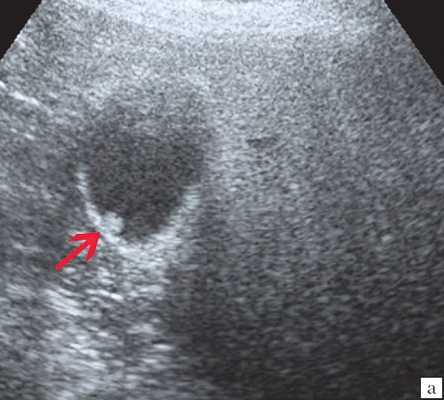

Ультрасонография является эффективным средством выявления полиповидной формы холестероза 4. Традиционной считается следующая сонографическая характеристика холестериновых полипов: неподвижные гиперэхогенные структуры, которые не дают акустической тени и прикрепляются к стенке желчного пузыря. Контуры таких образований, как правило, ровные, а размеры таких образований различны, чаще не превышают 10 мм (рис. 2).

![Эхограмма - одиночный полип в желчном пузыре (2а)]()

a) Одиночный полип в желчном пузыре (гиперэхогенное пристеночное неподвижное образование, с ровными контурами, без акустической тени).

Однако, по некоторым данным, размеры холестериновых полипов могут быть более 20 мм. Кроме того, полипы больших размеров (в 7% от общего числа) могут иметь пониженную эхогенность и фестончатый контур.

Мелкие холестериновые включения, образующие диффузную сеточку в толще подслизистого слоя размерами 1-2 мм, выглядят как локальное утолщение или уплотнение стенки желчного пузыря и в некоторых случаях (см. рис. 2) вызывают реверберацию (эхографический симптом "хвост кометы").